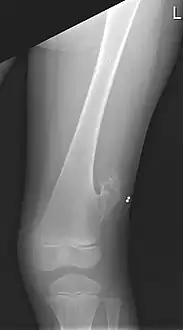

صورة بالأشعة السينية لعظم الفخذ الأيسر لصبي يبلغ من العمر 10 سنوات مع عرن في الجانب الوحشي، فوق الركبة بقليل.